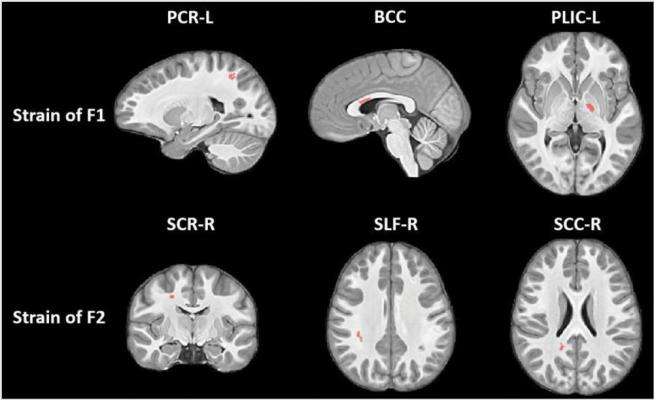

Long Term White Matter Changes After Severe Traumatic Brain Injury A 5 Year Prospective Cohort American Journal Of Neuroradiology

Cerebral Corticospinal Tract Injury Resulting From High Voltage Electrical Shock American Journal Of Neuroradiology